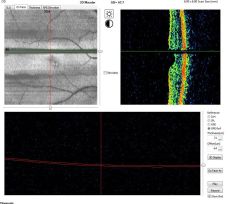

Optical coherence tomography (OCT) is a noninvasive diagnostic technique that renders an in vivo cross-sectional view of the retina. OCT utilizes a concept known as interferometry to create a cross-sectional map of the retina that is accurate to within at least 10-15 microns. OCT was first introduced in 1991 by Huang and colleagues[1] and has found many uses outside of ophthalmology, where it has been used to image certain nontransparent tissues. Due to the transparency of the eye (ie, the retina can be viewed through the pupil), OCT has gained wide popularity as an ophthalmic diagnostic tool.

At its inception, OCT images were acquired in a time-domain fashion. Time-domain systems acquire approximately 400 A-scans per second using 6 radial slices oriented 30 degrees apart. Because the slices are 30 degrees apart, care must be taken to avoid missing pathology between the slices.

Spectral-domain technology,[2] on the other hand, scans approximately 20,000-40,000 A-scans per second. This increased scan rate and number diminishes the likelihood of motion artifacts, enhances the resolution, and decreases the chance of missing lesions. Spectral-domain systems increase the signal-noise ratio by image averaging multiple B-scans at the same location. Whereas most time-domain OCTs are accurate to 10-15 microns, newer spectral-domain machines may approach 3-micron resolution. Whereas most time-domain OCTs image 6 radial slices, spectral domain systems continuously image a 6 mm area. This diminishes the chance of inadvertently missing pathology. Spectral-domain systems typically operate at 800 nm-870 nm wavelengths, although longer wavelengths of 1050-1060 nm are being developed for deeper penetration in the tissue.

In the late 2000s, the advent of enhanced depth imaging (EDI)[3] allowed for better visualization of the choroid and choroidoscleral interface using the spectral domain system. EDI employed image averaging, which set the zero-delay line (ZDL) adjacent to the choroid.

Swept-source technology,[4] uses a wavelength-sweeping laser and dual-balanced photodetector, allowing for faster acquisition speeds of 100,000-400,000 A-scans per second. This technology uses longer wavelengths of 1050-1060 nm for deeper tissue penetration without the need for EDI. This wavelength provides an axial resolution of about 5.3 µm in tissue compared to the approximately 5 µm axial resolution of the standard 800 nm wavelength of commercial spectral domain devices. The enhanced axial resolution along with the faster scanning speeds, which allow for greater image averaging, improves image quality and the ability to visualize deeper structures in more detail.